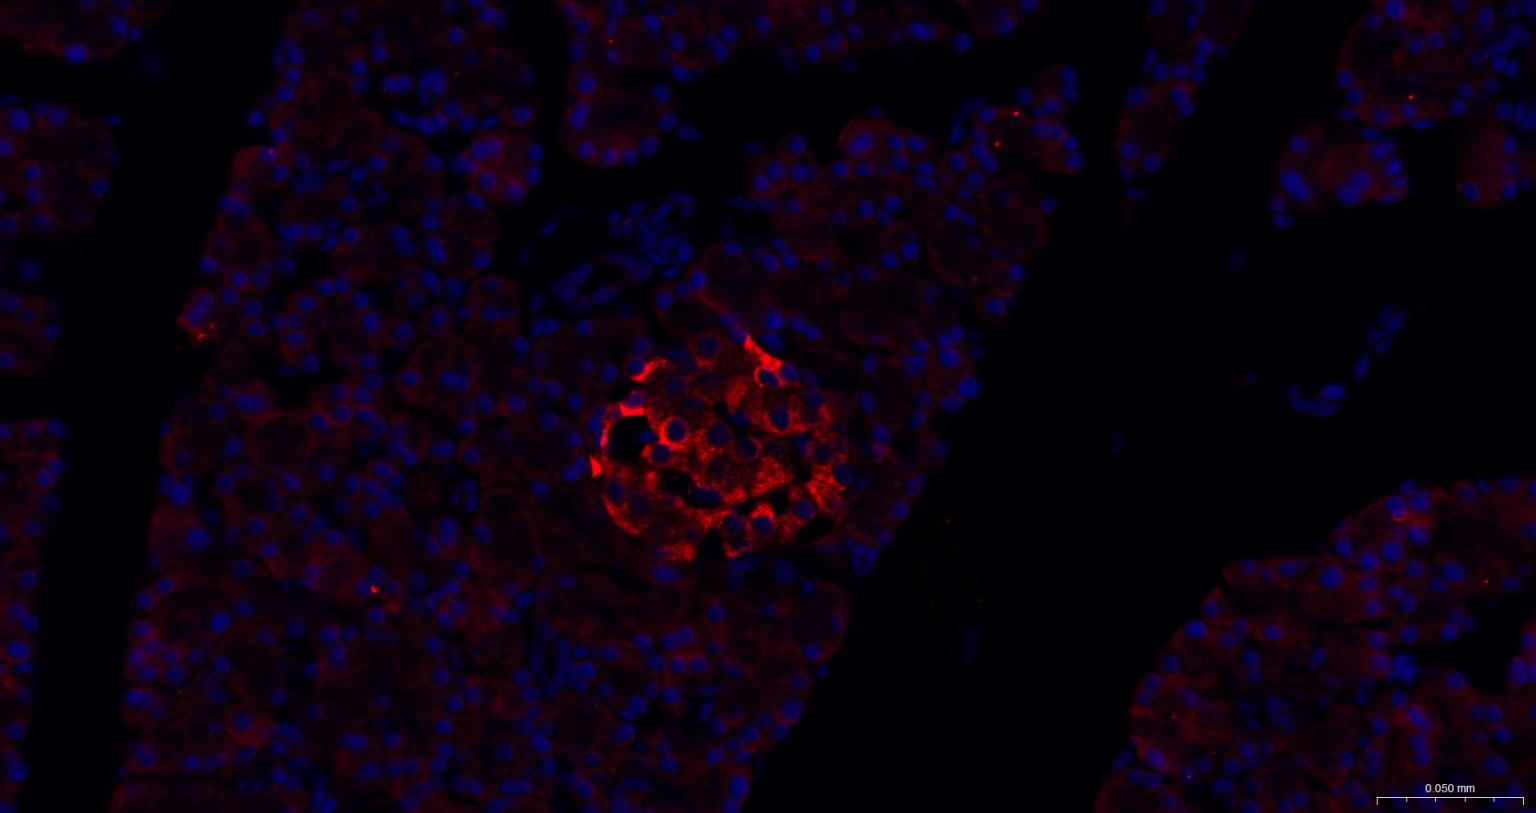

| IHC-P | Human, Mouse, Rat, Rabbit, Pig, Cow, Dog, Horse | 1:100-500 | |

| IHC-F | Human, Mouse, Rat, Rabbit, Pig, Cow, Dog, Horse | 1:100-500 | |

| IF | Human, Mouse, Rat | Rabbit, Pig, Cow, Dog, Horse | 1:100-500 |

交叉反应: Human, Mouse, Rat (predicted: Rabbit, Pig, Cow, Dog, Horse)